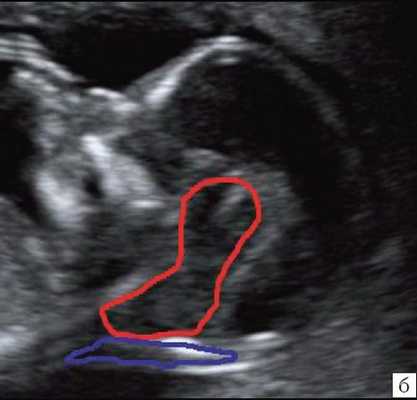

В то же время в среднесагиттальном скане была найдена расширенная большая цистерна, которая "сливалась" с IV желудочком, из-за отсутствия червя мозжечка. При осмотре "осьминожки" отсутствовала полноценная нижняя ножка, ввиду слияния ее с кистой в области большой цистерны (рис. 10).

Рис. 10. Аномалия Денди-Уокера, беременность 12 недель. Среднесагиттальный скан. Киста в области большой цистерны, сливающаяся с IV желудочком.

Визуализируется сосудистое сплетение IV желудочка на границе слияния.

Красный цвет - деформированная "осьминожка"; желтый цвет - киста в области большой цистерны; синий цвет - воротниковое пространство.